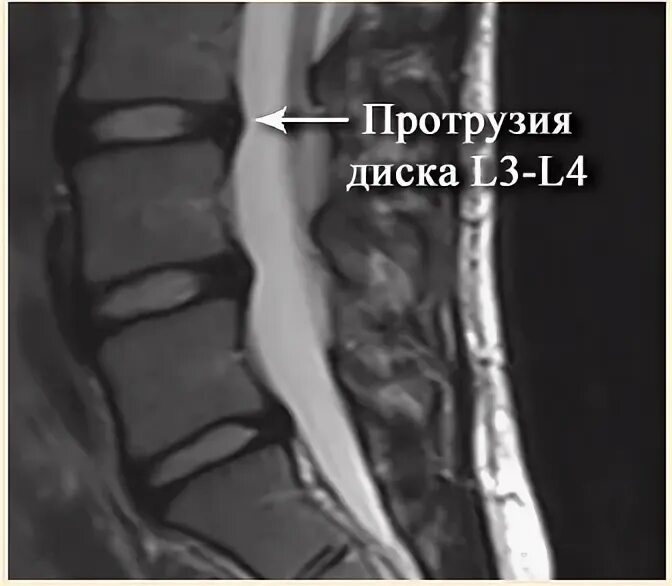

Диффузная протрузия межпозвонковых